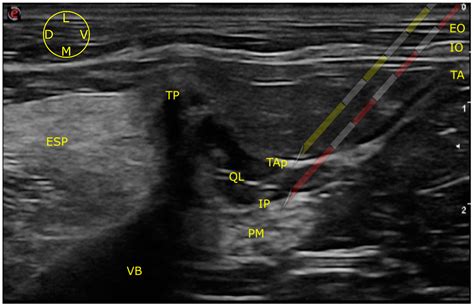

The ultrasound-guided technique has become the gold standard for performing a Femoral Nerve Block. It provides real-time visualization of the femoral nerve and surrounding structures, reducing the risk of complications and improving the success rate. The steps are as follows:

2. Place the ultrasound probe transversely over the inguinal crease to visualize the femoral nerve, artery, and vein.

3. Identify the femoral nerve, which appears as a hyperechoic structure lateral to the femoral artery.

4. Insert the needle in-plane with the ultrasound probe, aiming for the femoral nerve.

5. Aspirate to ensure the needle is not in a blood vessel, then inject the local anesthetic while visualizing the spread of the anesthetic around the nerve.